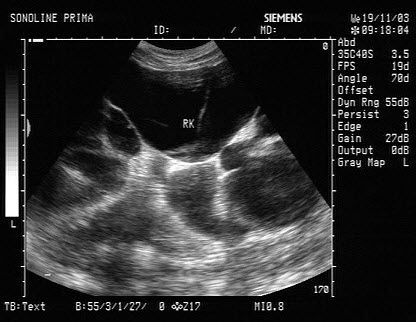

48、单项选择题

患者体检发现肝脏体积增大,超声见右叶巨大的强回声光团,边界见声晕,门脉见实质性光团充填,如图所示,考虑为()

A.肝癌并门脉癌栓

B.肝脓肿

C.肝囊肿

D.肝结核

E.肝血管瘤

49、单项选择题 下列对输尿管囊肿描述,错误的是()